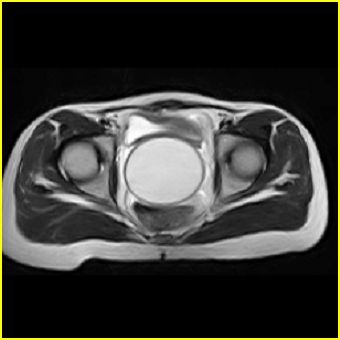

女、15岁、下腹疼痛2天,排尿困难1天。查体:处女膜闭锁,距处女膜约4至5cm处扪及一约5cm直径的圆形包块,张力较高,触痛明显、欠活动。b超提示子宫增大伴宫内增强回声团。

影像意见:子宫直肠陷凹积血。

更正影像意见:阴道积血。

处女膜闭锁,阴道积血

处女膜闭锁,阴道积血,子宫积血.

先天性处女膜闭锁,伴阴道积血,不除外先天性阴道粘液囊肿形成。

阴道积血,子宫积血.

子宫及阴道积血。

处女膜闭锁,伴子宫及阴道积血.